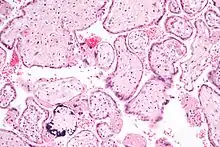

| Micrograph of cytomegalovirus (CMV) infection of the placenta (CMV placentitis), a vertically transmitted infection: The characteristic large nucleus of a CMV-infected cell is seen off-centre at the bottom right of the image, H&E stain. | |

CMV placentitis